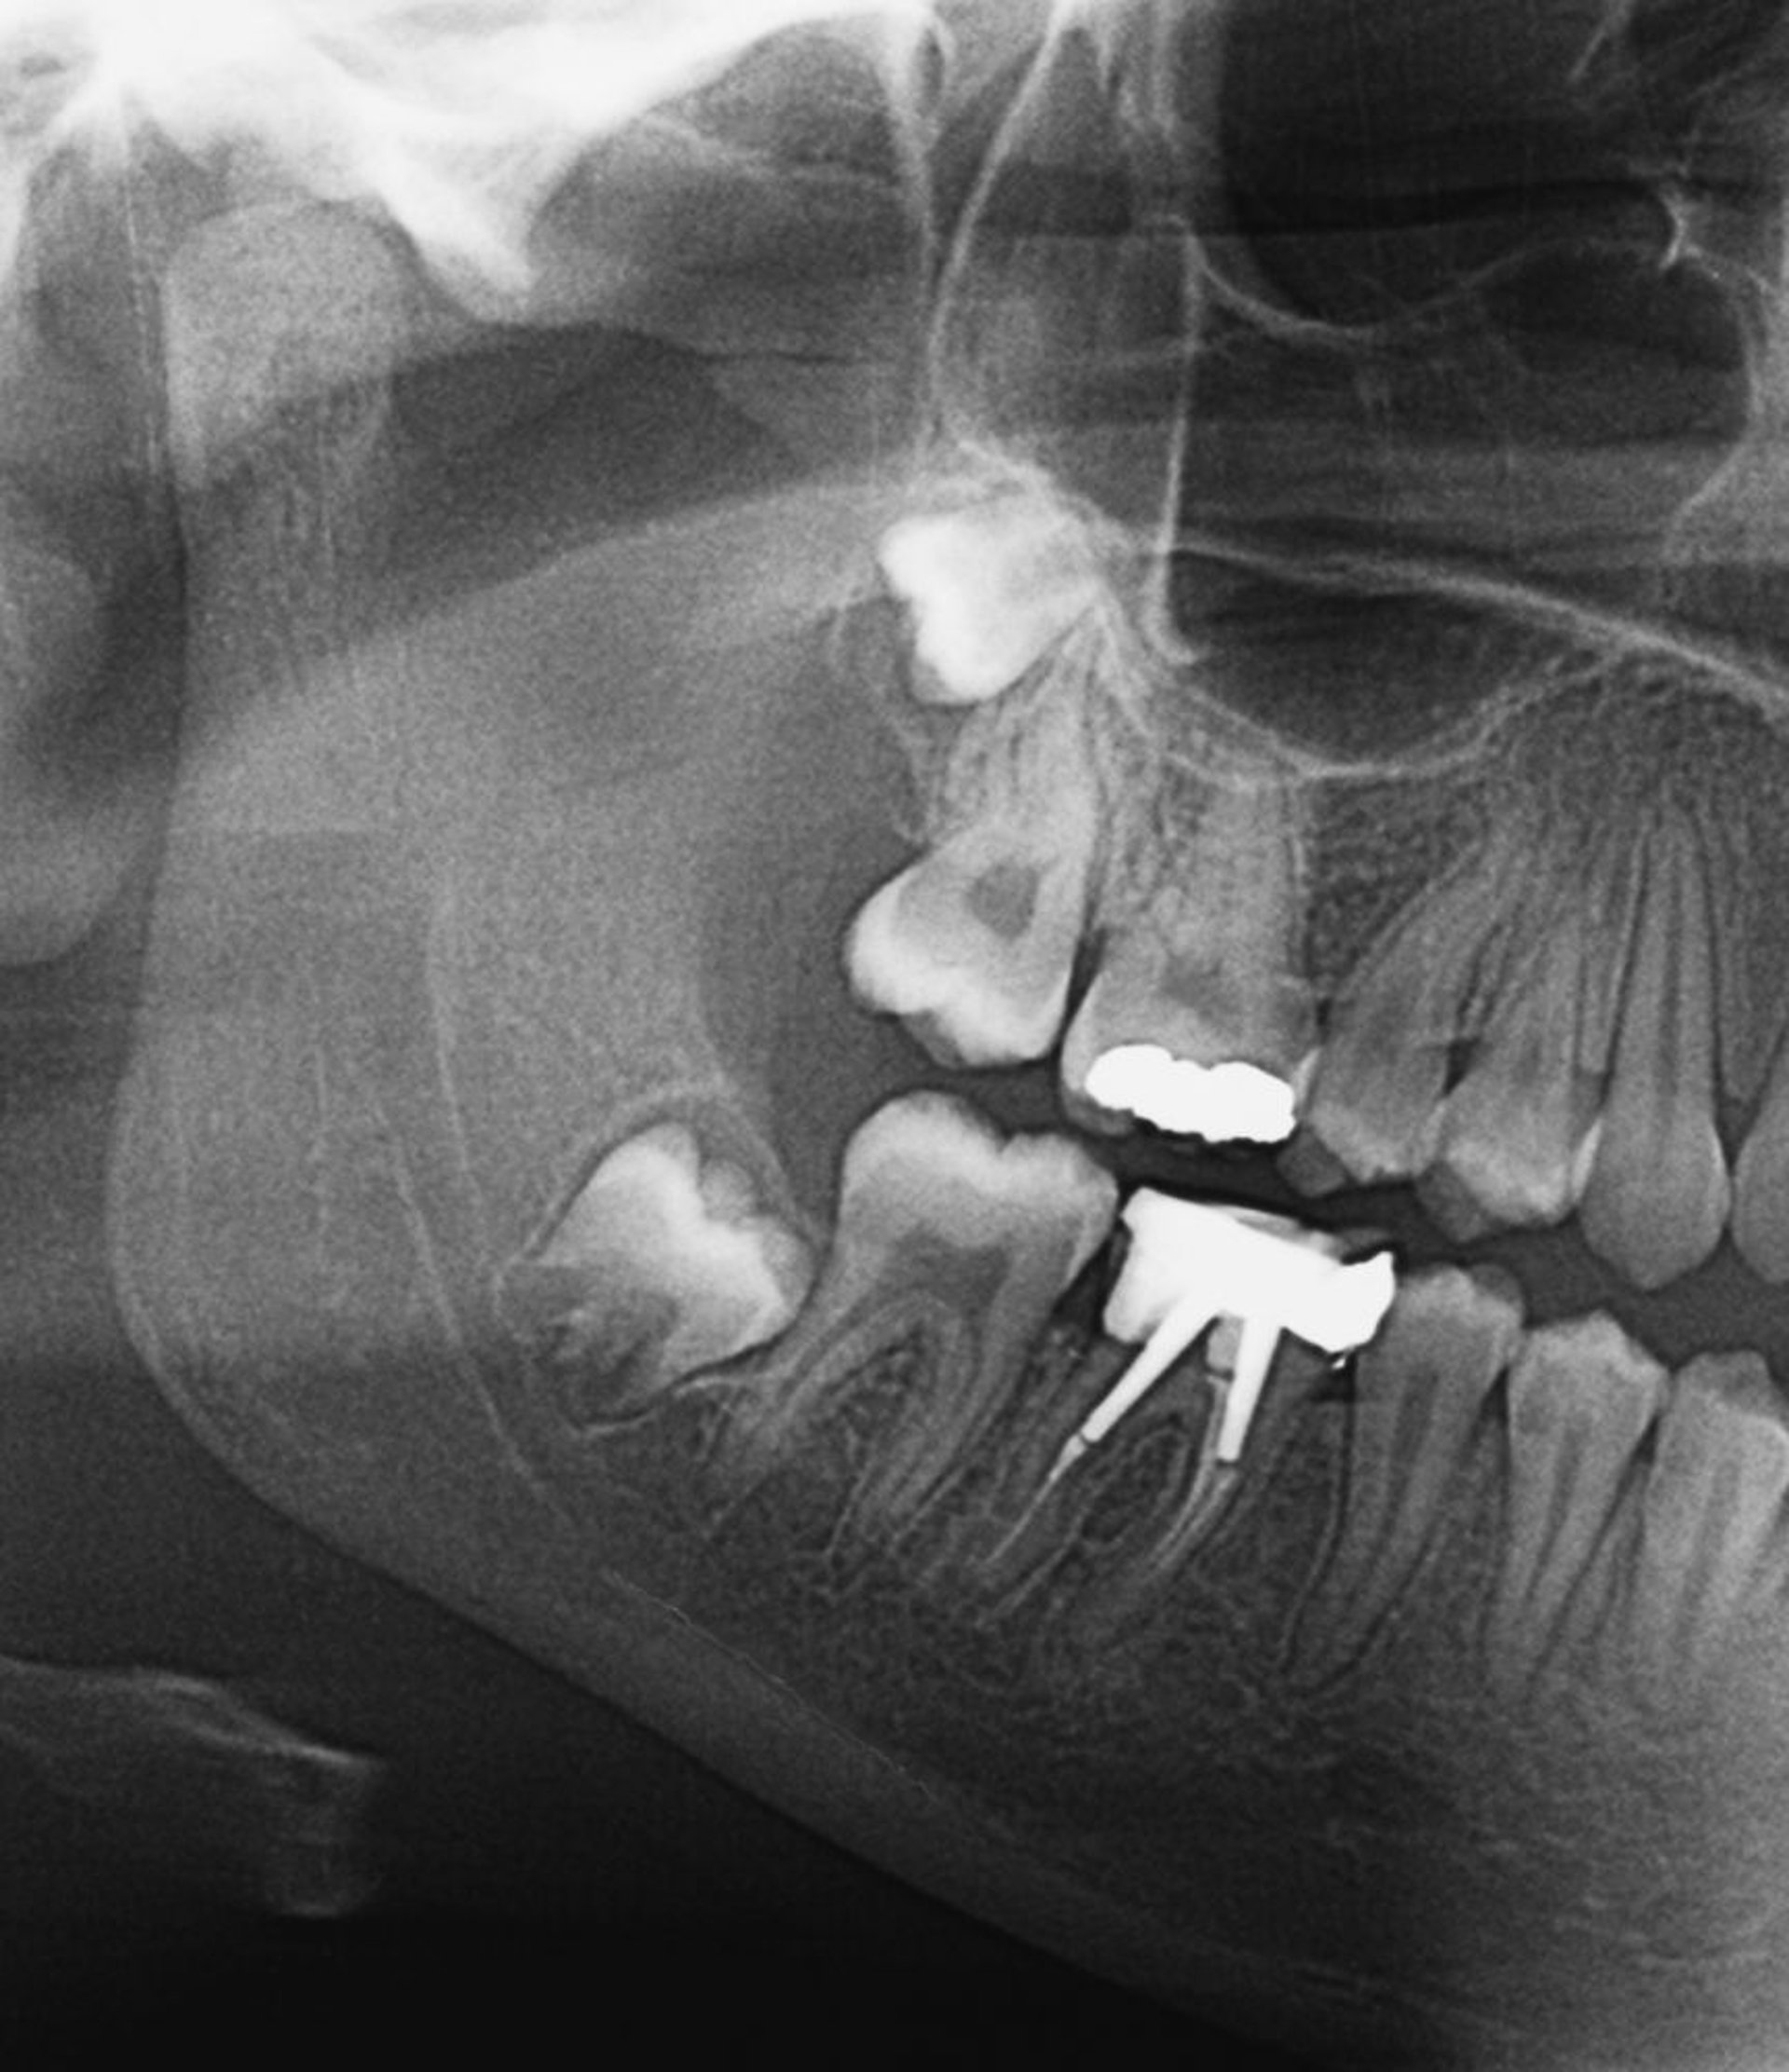

Dieses Röntgenbild zeigt impaktierte Weisheitszähne. Wenn die Weisheitszähne durchbrechen oder teilweise impaktiert sind, kann sich eine Perikoronitis entwickeln.